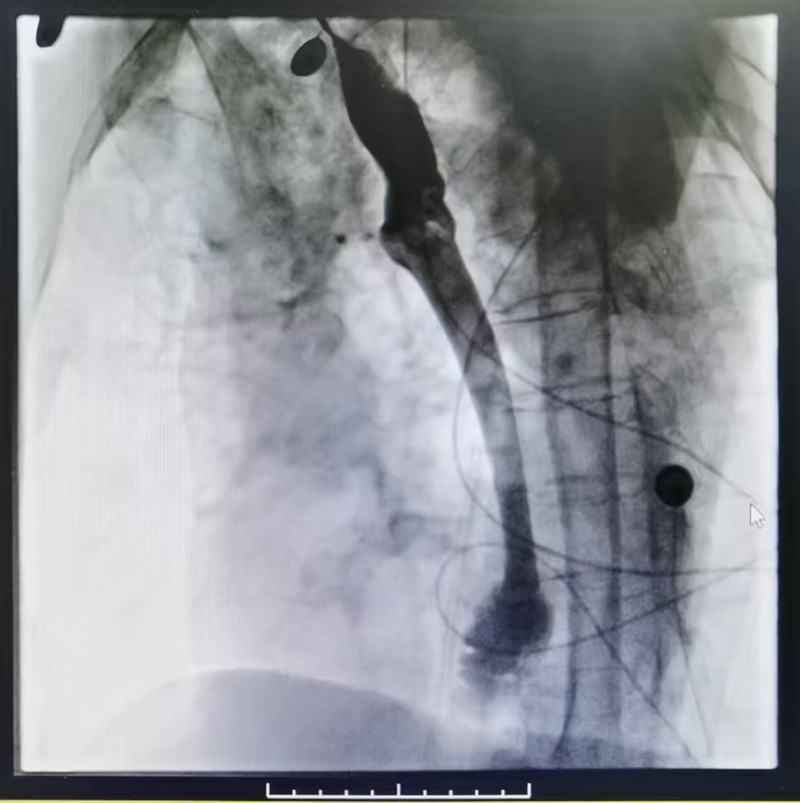

术后造影剂通过顺利

该手术是以DSA为引导,把食管支架准确无误植入在食管狭窄的部位,将患者食道狭窄处撑开,形成通道,从而解决患者进食难的问题。食管支架植入术具有创伤小、疗效高、风险低、并发症少、住院时间短等优点,既解决了食管梗阻所致的严重摄入障碍,又改善了病人的生活质量。